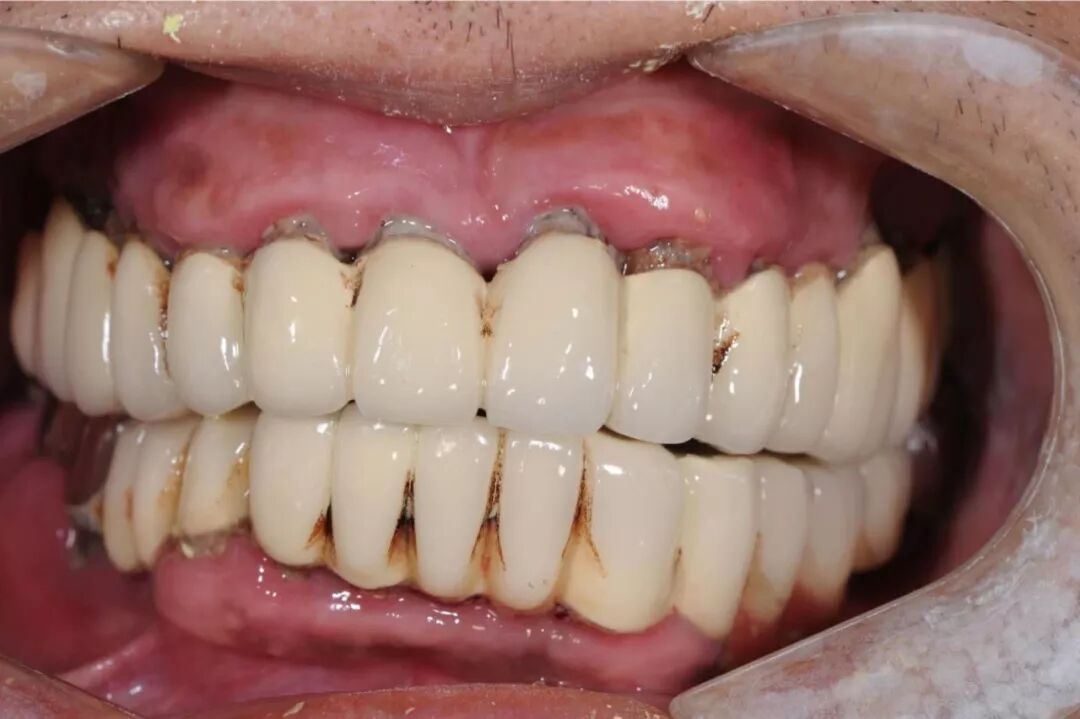

接下来再谈谈另一种不太与时俱进的烤瓷修复方式,即四环素牙和某些牙色不佳患者的全口烤瓷美容,同样的道理,十几年前因技术局限而造成相当部分患者被磨小了全口牙齿戴了烤瓷牙,以牺牲牙质的代价换取了阶段性的美观,后期乃至一辈子都在为不断出现的并发症而伤透脑筋。我们可以百度一下“明星做烤瓷牙”,百度虽说在涉及医疗的资讯上很不靠谱,但涉及明星的个人颜值信息搜索上却是相当全面。

全口牙磨小后是个什么状态,烤瓷以后又是什么效果,因人而异,但无论美观上做得多好,长期隐患如同不定时炸弹,多磨一颗牙就多一分风险。